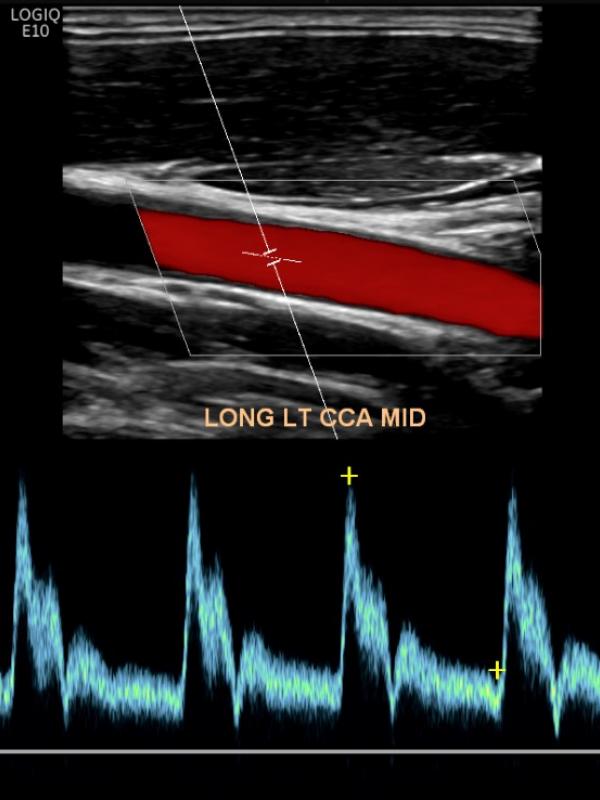

Carotid ultrasound

Ultrasound imaging of the carotid arteries evaluates for plaque build-up or blockage. Referring providers order carotid ultrasound for a number of reasons. The most common reasons are: dizziness, stroke, blurred vision, or bruit discovered on physical exam.